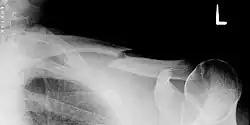

Häufig ergibt sich schon bei der klinischen Untersuchung die Diagnose durch lokale Schwellung, Druckschmerz, tastbare Knochenenden unter der Haut oder Knochenreiben (Krepitation). Die Diagnose wird durch eine Röntgenuntersuchung bestätigt.